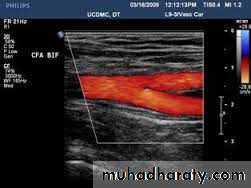

Doppler ultrasoundDuplex ultrasound

Duplex ultrasound

DopplerDuplex ultrasound